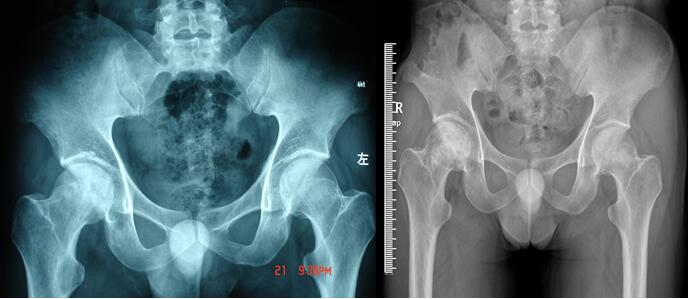

玉林市中西医结合骨科医院——骨病骨肿瘤股骨头坏死专科,是全国股骨头坏死保髋联盟成员单位,玉林市中医重点专科建设单位,是广西区内较早成立的、专注于股骨头坏死、骨病与骨肿瘤的特色科室。科室深耕上述疾病领域多年,始终恪守“精准诊疗、微创为先、中西结合”的理念,吸引了大量区内外患者慕名求医,每年开展的髋关节置换手术超千台,以精湛技术为众多患者重塑行走希望。